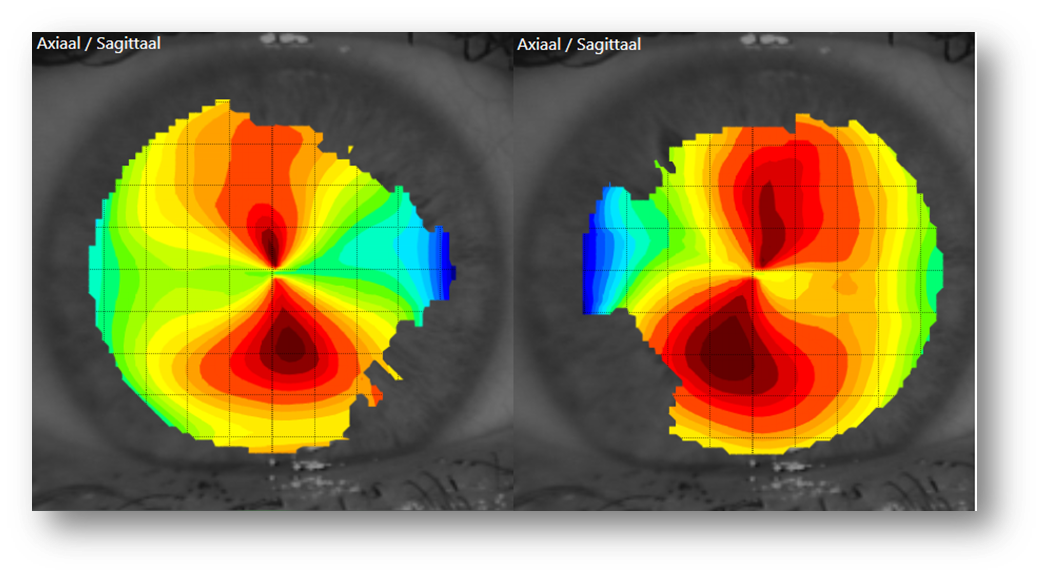

Als je de onderstaande afbeeldingen bekijkt, wat is het eerste wat in je op komt? Keratoconus suspect?

De initiële topobeelden gaven reden tot twijfel of er sprake zou kunnen zijn van een keratoconus (suspect).

Op basis van alleen topografiebeelden kunnen we niet concluderen of er wel of geen sprake is van een keratoconus (suspect), daarvoor is onder andere pachymetrie nodig. De klant was niet bekend met eventuele (familiaire) cornea-afwijkingen en uit de anamnese kwamen geen verdere bijzonderheden. We besloten om voor een periode van minimaal drie weken, wekelijks topografiebeelden te maken en een refractie uit te voeren, om te zien wat er zou gebeuren.